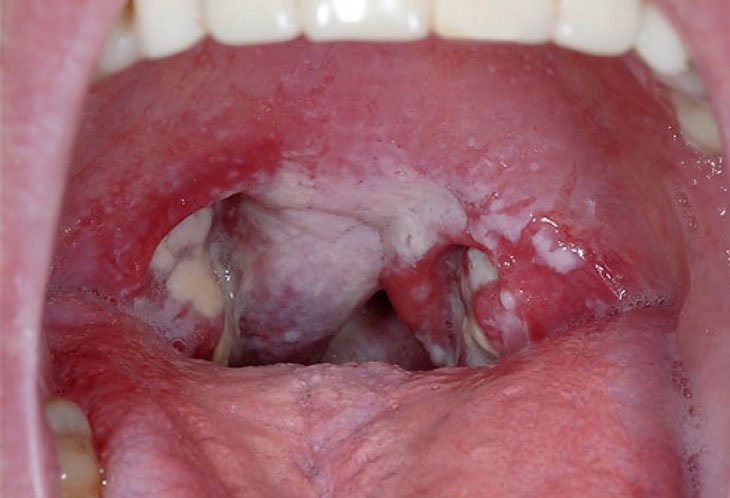

- Triệu chứng bệnh chủ yếu là viêm họng, có lớp màng giả màu trắng do các tế bào bị viêm bám vào trong vòm họng.